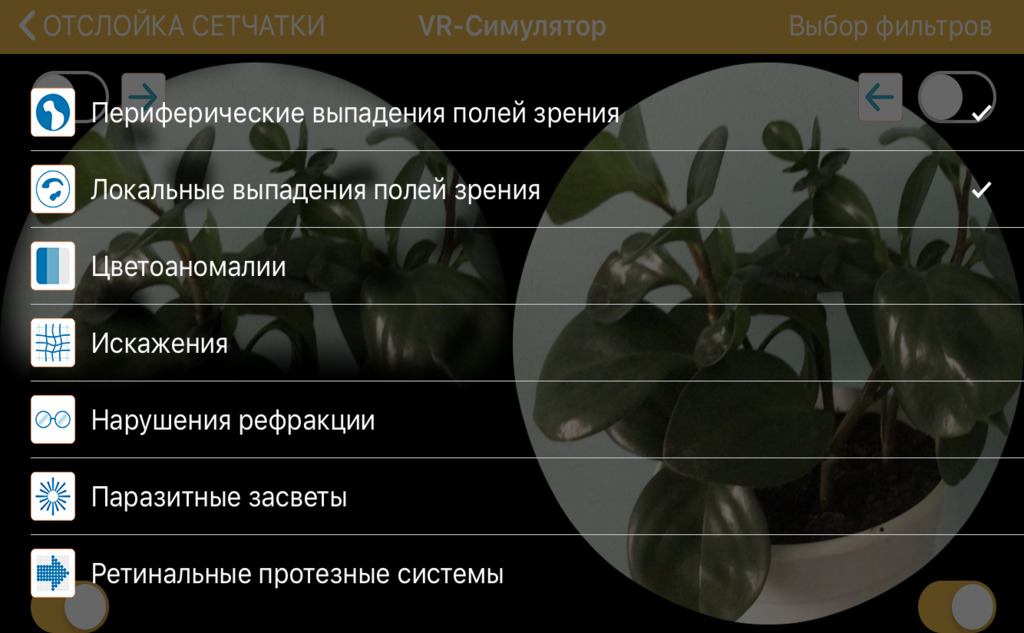

Некоторые болезни комбинированные. Чтобы подключить еще один фильтр, смахните экран слева направо и выберите дополнительные условия симуляции патологии. Для каждой болезни подходят только определенные фильтры, поэтому вам придется поочередно выбирать все варианты и смотреть на результат.